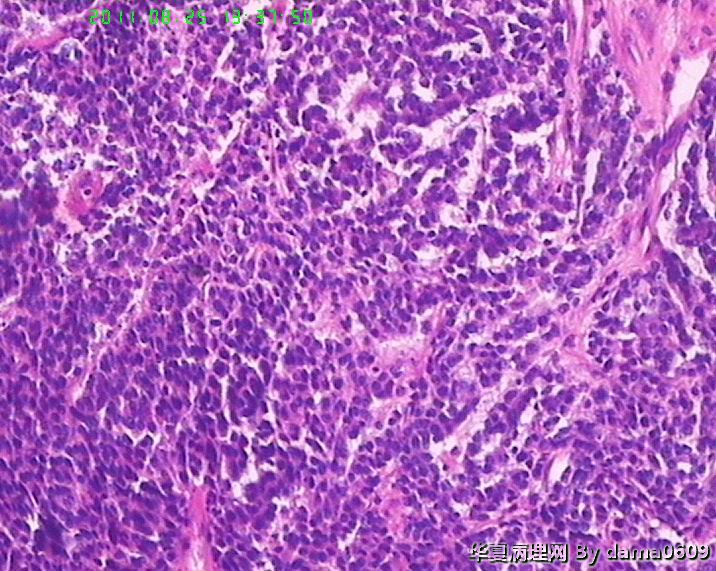

患者男性,39岁。以回盲部肿物行肠镜检查、活检。镜下四块组织内有两块见呈巢状的小细胞(如图

),另两块为粘膜慢性炎表现及坏死组织。学生不知如何分类:未分化癌?类癌?小细胞癌?请老师指教。谢谢!

细胞核较小、深染、一致,核分裂象少见,支持典型类癌。

神经内分泌肿瘤 淋巴瘤 低分化腺癌。。。

又仔细看了一下片子,有核仁,见到核分裂,是否可以定“未分化腺癌”呢?

楼主是想说“未分化癌”?片子切的比较厚,考虑神经内分泌肿瘤,低分化腺癌待排。